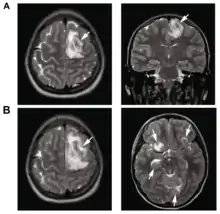

B: T1-weighted MRI showing expansion of the brain lesions 4 days later